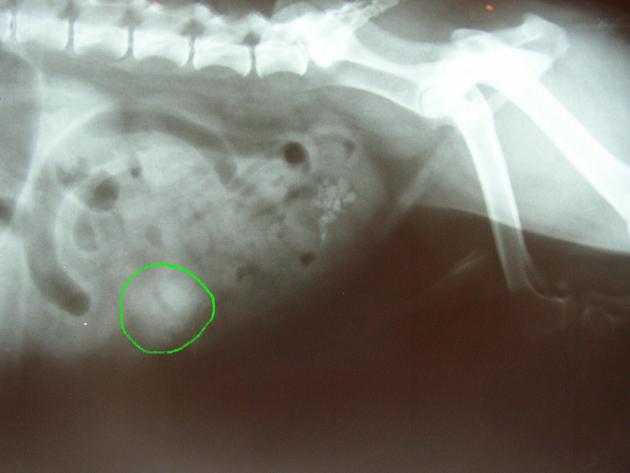

La présence de certains corps étrangers peut être suspectée voire directement révélée par une radiographie simple: une dilatation de l’estomac et la présence d’air sur une radiographie abdominale de lapin feront très fortement suspecter la présence de trichobézoards tandis que des objets métalliques ou des os seront directement visibles sur le cliché radiographique de l’abdomen d’un chien.

en vert: corps étranger dans l’abdomen d’un chien (il s’agissait d’un morceau de caoutchouc)

(la radiographie révèle également la présence de calculs dans la vessie)